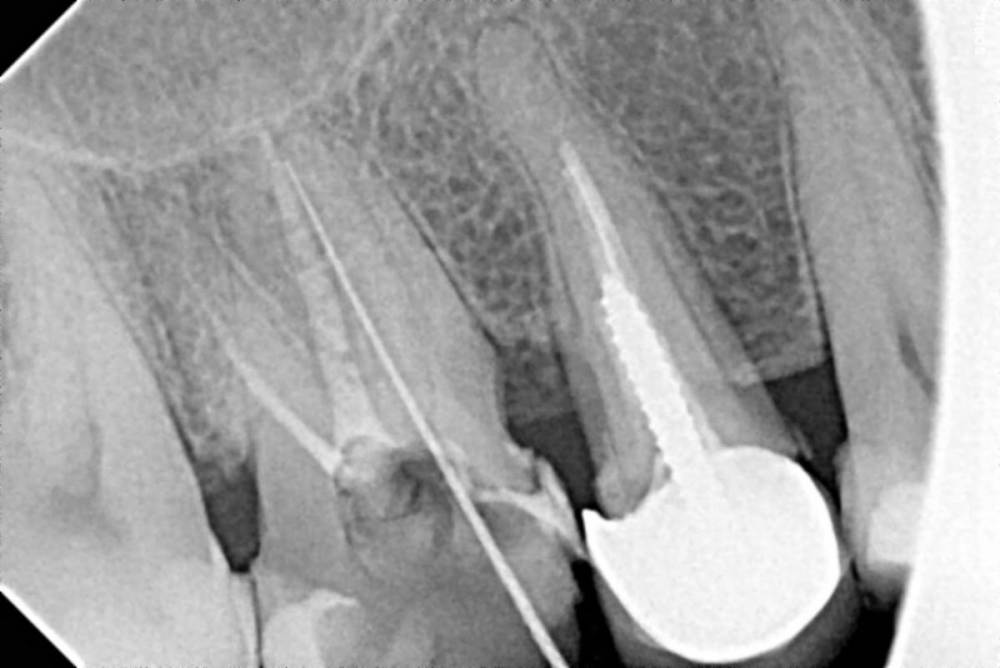

Рабин Опубликовано 31 марта, 2021 Поделиться Опубликовано 31 марта, 2021 Дорогие врачи, подскажите советом и есть ли вина ортопеда после постановки коронок. Неделю назад ставила 2 коронки на 5 и 6 верхние зубы. Примерно через 4 дня на десне над 6 зубом образовался свищ. Хирург на осмотре определил, что это киста и вычистил её кюретажом десны (за мои деньги) До этого 6 зуб был пролечен, каналы и т. д, но до одного корня невозможно было добраться, лечили его давно. Я специально понаблюдала за зубом в течение 2 месяцев, перед тем как ставить коронку на этот 6 проблемный зуб. Все было отлично! Но вот после того как ортопед поставил коронки выскочила эта киста на зубе. Совпадение? Скажите, может ли из-за некорректного протезирования, образоваться киста на зубе? 15 лет зуб этот не беспокоил, даже с непроходимым каналом... Дело в том, что ортопед работал без перчаток, при обточке зуба под коронку было много крови... Естественно десна воспалилась... Прилагаю фото рентгена. Скажите, чем грозит мне в будущем зуб, если на нём прочистил хирург кисту. И нужно ли снимать свежую коронку? И смотреть что там с зубом внутри и не подлежит ли он удалению? Гарантия на эти коронки у меня год. Ортопед предлагает ходить с ней дальше, если не заболит. Спасибо за ответы заранее. Очень переживаю за эту ситуацию и не вылезаю уже из больницы после протезирования. Скажите правильно ли поставлены коронки и пролечены каналы у 6 зуба? Скрытый текст Ссылка на комментарий

chervoncevdaniil Опубликовано 1 апреля, 2021 Поделиться Опубликовано 1 апреля, 2021 Ортопед своими действиями занести туда обострение не мог,это произошло потому,что у вас непролечен канал и вы судя по всему осознанно шли на этот риск. Вылечить "кисту"без пломбировки корневого канала невозможно,потому что там сейчас целый канал с инфекцией,которая никуда не денется,просто обострения могут со временем стихать и заново повторяться Ссылка на комментарий

Рабин Опубликовано 1 апреля, 2021 Автор Поделиться Опубликовано 1 апреля, 2021 4 часа назад, chervoncevdaniil сказал: Ортопед своими действиями занести туда обострение не мог,это произошло потому,что у вас непролечен канал и вы судя по всему осознанно шли на этот риск. Вылечить "кисту"без пломбировки корневого канала невозможно,потому что там сейчас целый канал с инфекцией,которая никуда не денется,просто обострения могут со временем стихать и заново повторяться Спасибо за ответ! Скажите, если не снимать коронку, как предлагает ортопед, может ли киста пойти и на соседний 5 зуб? И скажите, видите ли вы воспаление на данных снимках? Я пошла на это осознанно, так как все врачи твердили, что у меня нет на зубе воспаления, корни хорошие, можно ставить коронку, несмотря на то, что один канал резорцирован. Он меня ранее 10 лет не беспокоил. Спасибо! Ссылка на комментарий